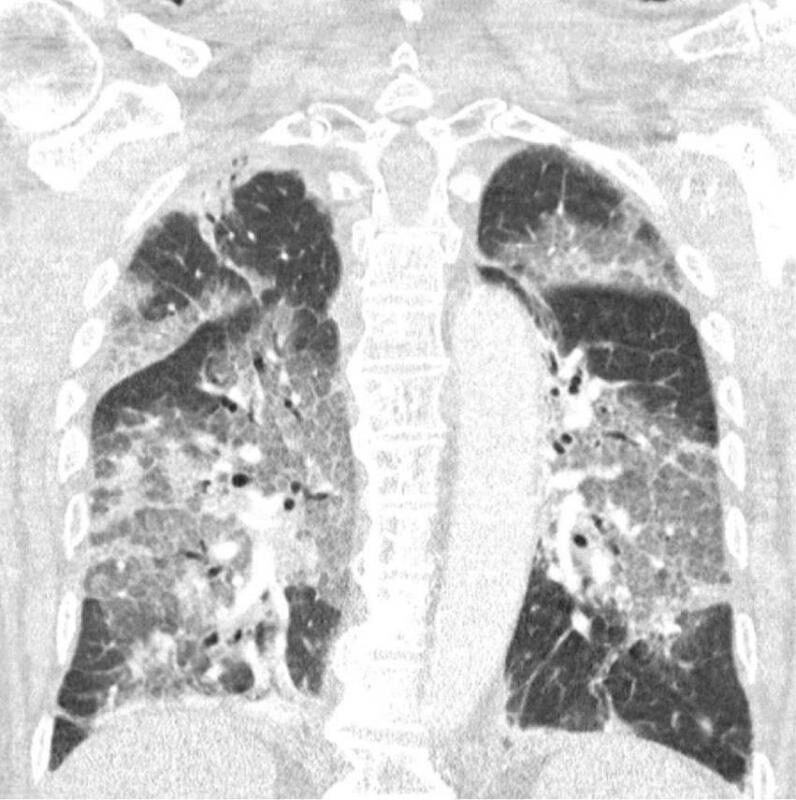

En la carta relatan el ingreso en la UCI de un paciente que se ha negado a recibir la vacuna de AstraZeneca. Comentan con detalle como lucha por su vida, conectado a la respiración asistida: "Oímos el tremendo pesar en su voz y la desesperación en sus ojos. El virus lo ha atacado y podría haberse evitado. Con su permiso, compartimos su escáner de pulmón. No es necesario ser un especialista en pulmones para reconocer la devastación, ni epidemiólogo para explicar los riesgos de no estar vacunado".